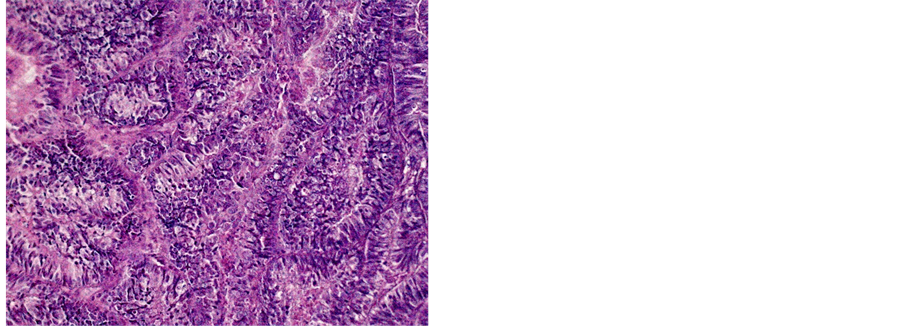

Figure 5. Well differentiated ADK (a) 200×, (b) 400×.

Histologically, SCC was the predominant type with 1.687 (81.18%) cases, followed by the ADK with 269 (12.95%) cases. This predominance of the EC was discovered by several African authors. It is notably higher than the value found in the Cameroonian coast (72, 07%) [8] . Other studies have assigned even higher values: Sando et al. −87.6%, Hasiniatsy et al. −88.50%, Nayama et al. −91.6% and Elmajjawi et al. −94% [7] [16] [17] [25] . However, in the West, Mubiayi et al. reported a trend applicable to ours with 81% cases of squamous cell carcinoma. However, more cases of adenocarcinoma were registered in their series, 17% [26] . According to studies, cervical squamous cell carcinoma risk is 74% - 80% higher in women with a first-degree relative with cervical squamous cell carcinoma, compared to the general population [27] . Cervical adenocarcinoma risk is 39% - 69% higher in women with a first-degree relative with cervical squamous cell carcinoma, compared to the general population, a number of studies showed [27] . Cervical squamous cell risk is 15% higher in women who have had 1 full-term pregnancy than in those who have never had; the risk increases with the number of full- term pregnancies [28] . The same study showed that cervical cancer risk among parous women is 77% higher in those under 17 at their first full-term pregnancy than in those aged 25 or more; the risk decreases with age at first full-term pregnancy [28] . There is no association with parity for adenocarcinoma [28] . Cervical squamous cell carcinoma risk is 1.5 times higher in current smokers than in people who have never smoked, and the risk increases with the number of cigarettes smoked per day [14] .